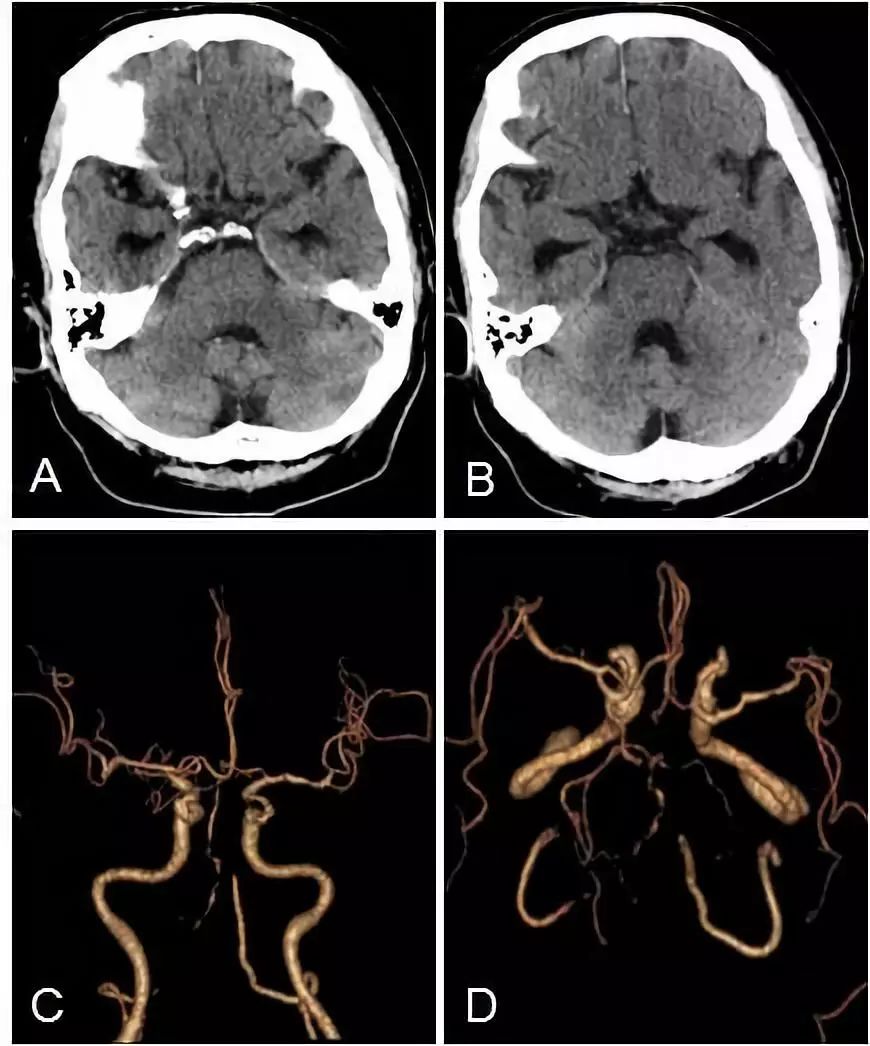

头颅CT+CTA:脑干及小脑半球多发梗死(图3A,B),双椎动脉V4段闭塞,基底动脉近段重度狭窄(图3C,D)。

图3